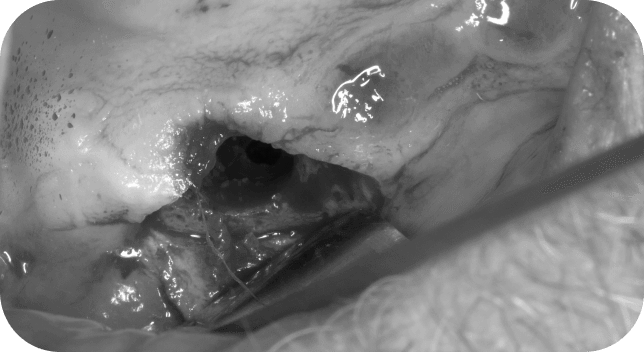

Get a detailed understanding of the technique of conducting an open and closed sinus lift, which will allow you to ensure stable results.

Direct or Indirect Sinus Lift. OPERATION TECHNIQUE

Learn how to work in complicated situations - perform a direct sinus lift surgery with 1 mm of residual bone.

RESIDUAL BONE IS 1 MM. WHAT TO DO?

Get an action plan for managing the membrane perforation, learn how to prevent inflammation and get to know the postsurgery prescriptions.

PERFORATION OF THE SCHEIDERIAN MEMBRANE